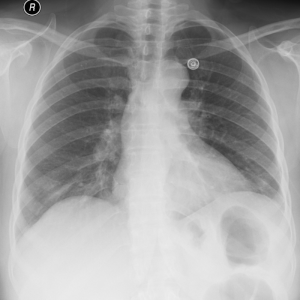

An empyema (/ˌɛmpˈmə/) is a collection of pus within a naturally existing anatomical cavity. For example, pleural empyema is empyema of the pleural cavity. It must be differentiated from an abscess, which is a collection of pus in a newly formed cavity. The term is from Greek ἐμπύημα, "abscess".

Lungs[edit | edit source]